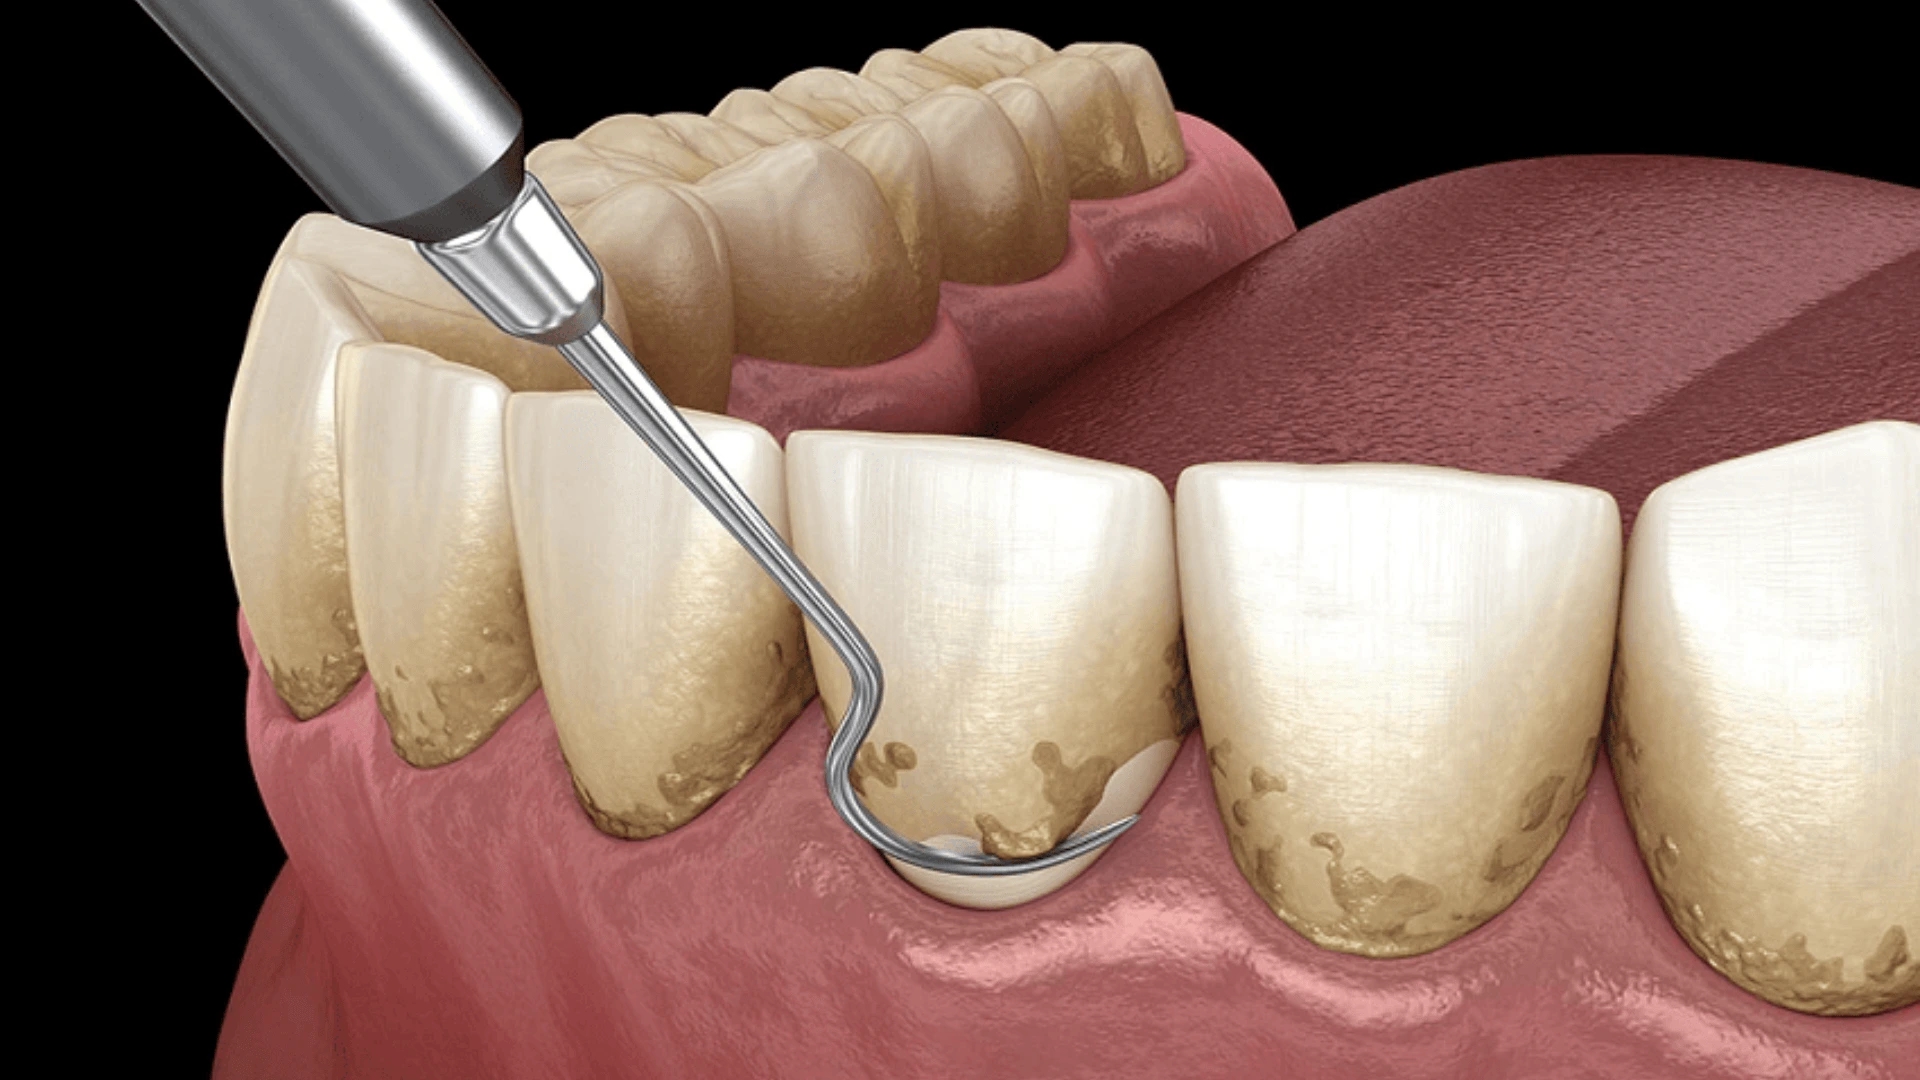

جرمگیری لثه یک روش درمانی در دندانپزشکی است که به پاکسازی جرمها و پلاکهای انباشتهشده روی دندانها و در نواحی اطراف و زیر لثه کمک میکند. این روش برای حفظ سلامت لثهها و جلوگیری از مشکلاتی مانند التهاب، خونریزی و حتی تحلیل لثه ضروری است. تجمع جرم و پلاک روی دندانها بهمرورزمان میتواند باعث بروز بیماریهای لثهای مانند ژنژیویت (التهاب لثه) و پریودنتیت (بیماری پیشرفته لثه) شود.

با انجام جرمگیری، دندانپزشک از ابزارهای ویژهای برای برداشتن لایههای سخت شده جرم استفاده میکند. جرمهای دندانی معمولاً از مواد معدنی موجود در بزاق، باقیمانده غذاها و باکتریهای مضر تشکیل میشوند. با جرمگیری لثه، میتوانید به جمع ۵۲ درصدی افراد سالم بپیوندید. این اقدام پیشگیرانه، نهتنها از تحلیل لثه جلوگیری میکند، بلکه احتمال ابتلا به بیماریهای قلبی و عروقی را تا ۲۰% کاهش میدهد. هر ۶ ماه یکبار، با جرمگیری لثه، سرمایهگذاری پرسودی روی سلامت خود انجام دهید.

جرمگیری دستی (اسکیلینگ دستی)

در این روش، دندانپزشک از ابزارهای دستی مخصوصی به نام کورت و اسکیلر استفاده میکند تا جرمهای سخت شده را از سطح دندان و زیر لثه جدا کند. این روش به دلیل دقت بالا معمولاً برای بیمارانی که میزان جرم آنها کم است یا دچار حساسیت لثه هستند، توصیه میشود.

بر خلاف جرمگیری دندان که تنها روی سطح دندان تمرکز دارد، جرمگیری لثه (که بهعنوان جرمگیری عمقی نیز شناخته میشود) برای حذف جرمهایی که در زیر خط لثه جمع شدهاند، استفاده میشود.

۲. جرمگیری زیر لثه (Scaling): در این مرحله، رسوبات سخت و باکتریهای مخفی در زیر خط لثه برداشته میشوند.

۳. ریشهتراشی (Root Planing): سطوح ریشه دندان صاف میشود تا از تجمع مجدد جرم و پلاک جلوگیری شود.